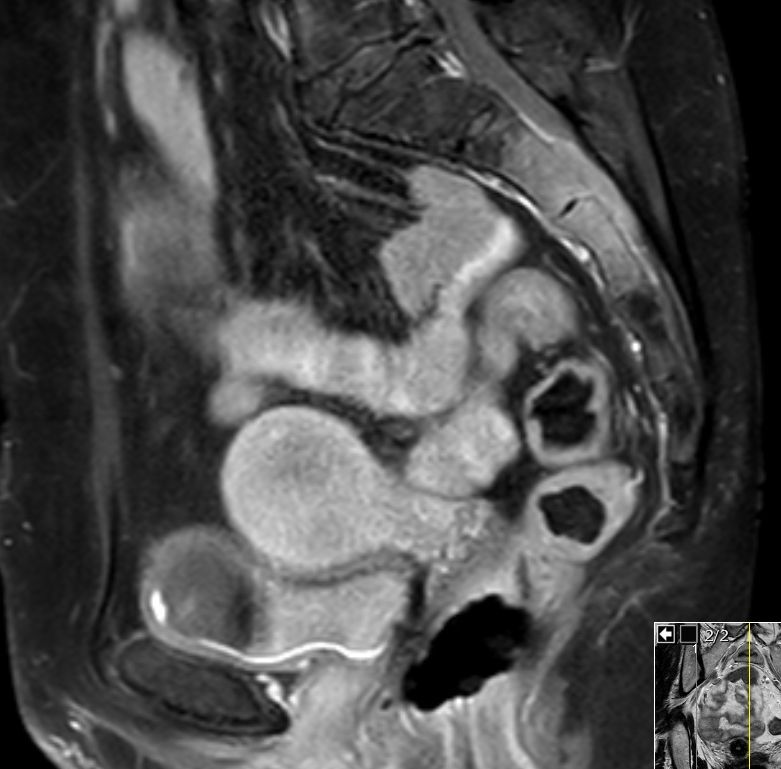

| Kreuzbein | 51jährige Bürokauffrau in leicht reduziertem AZ. KI 80.  Sie hat starke Schmerzen in der Kreuzbeinregion, so dass sie nicht auf dem Rücken liegen kann. Ferner besteht eine Blasenentleerungsstörung. Das MRT zeigt eine tumoröse Infiltration des 2. und 3. Kreuzbeinsegmentes. Der Tumor ist in den Spinalkanal eingebrochen und hat die Nerven der Cauda aequina eingehüllt. ![]()  |